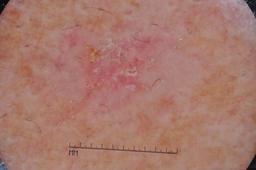

ISIC-DICM-17K (ISIC Dermoscopic Images and Clinical Metadata 17K) is a curated and balanced dataset derived from the International Skin Imaging Collaboration (ISIC) Archive Gallery. It comprises 17,060 dermoscopic images and clinical metadata (8,530 melanoma and 8,530 non-melanoma classes).

For more details, please follow the project’s GitHub repository: https://github.com/mmu-dermatology-research/isic-dicm-17k

This dataset was used in this study and benchmark to explore the effectiveness of multimodal learning for skin lesion classification:

S. Ahammed, X. Cui, W. Lu and M. H. Yap, "Skin Lesion Classification using Dermoscopic Images and Clinical Metadata: Insights from Multimodal Models," 2025 IEEE/CVF Conference on Computer Vision and Pattern Recognition Workshops (CVPRW), Nashville, TN, USA, 2025, pp. 222-230, DOI: 10.1109/CVPRW67362.2025.00027